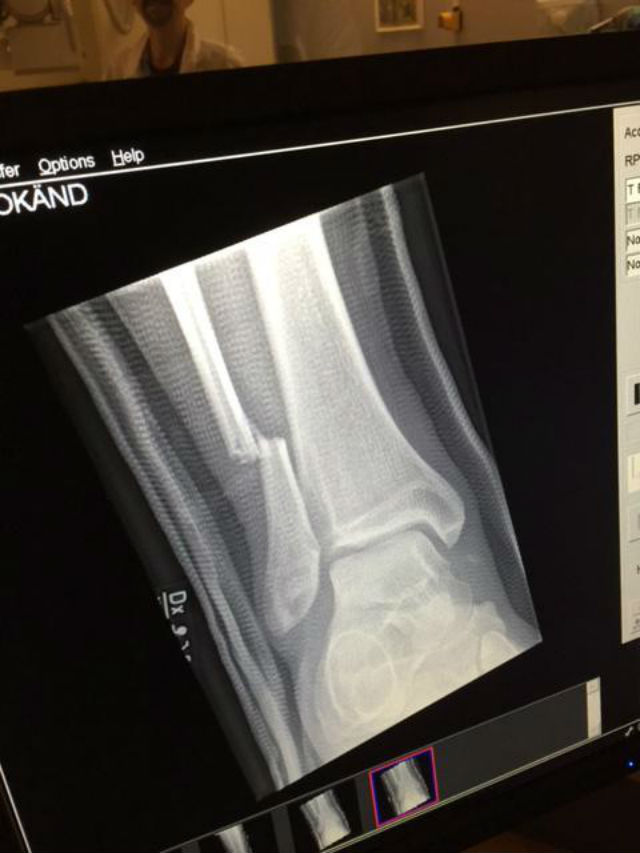

Și el a revenit, într-adevăr, pe scenă, după o oră, cu piciorul în ghips. Și-a terminat concertul, stând pe scaun sau sprijinindu-se pe cârje. La câteva ore după concert, trupa a publicat pe Twitter o radiografie a piciorului cântărețului în care se vede un os rupt, însoțită de cuvintele "Mulțumesc Goteborg, a fost minunat".